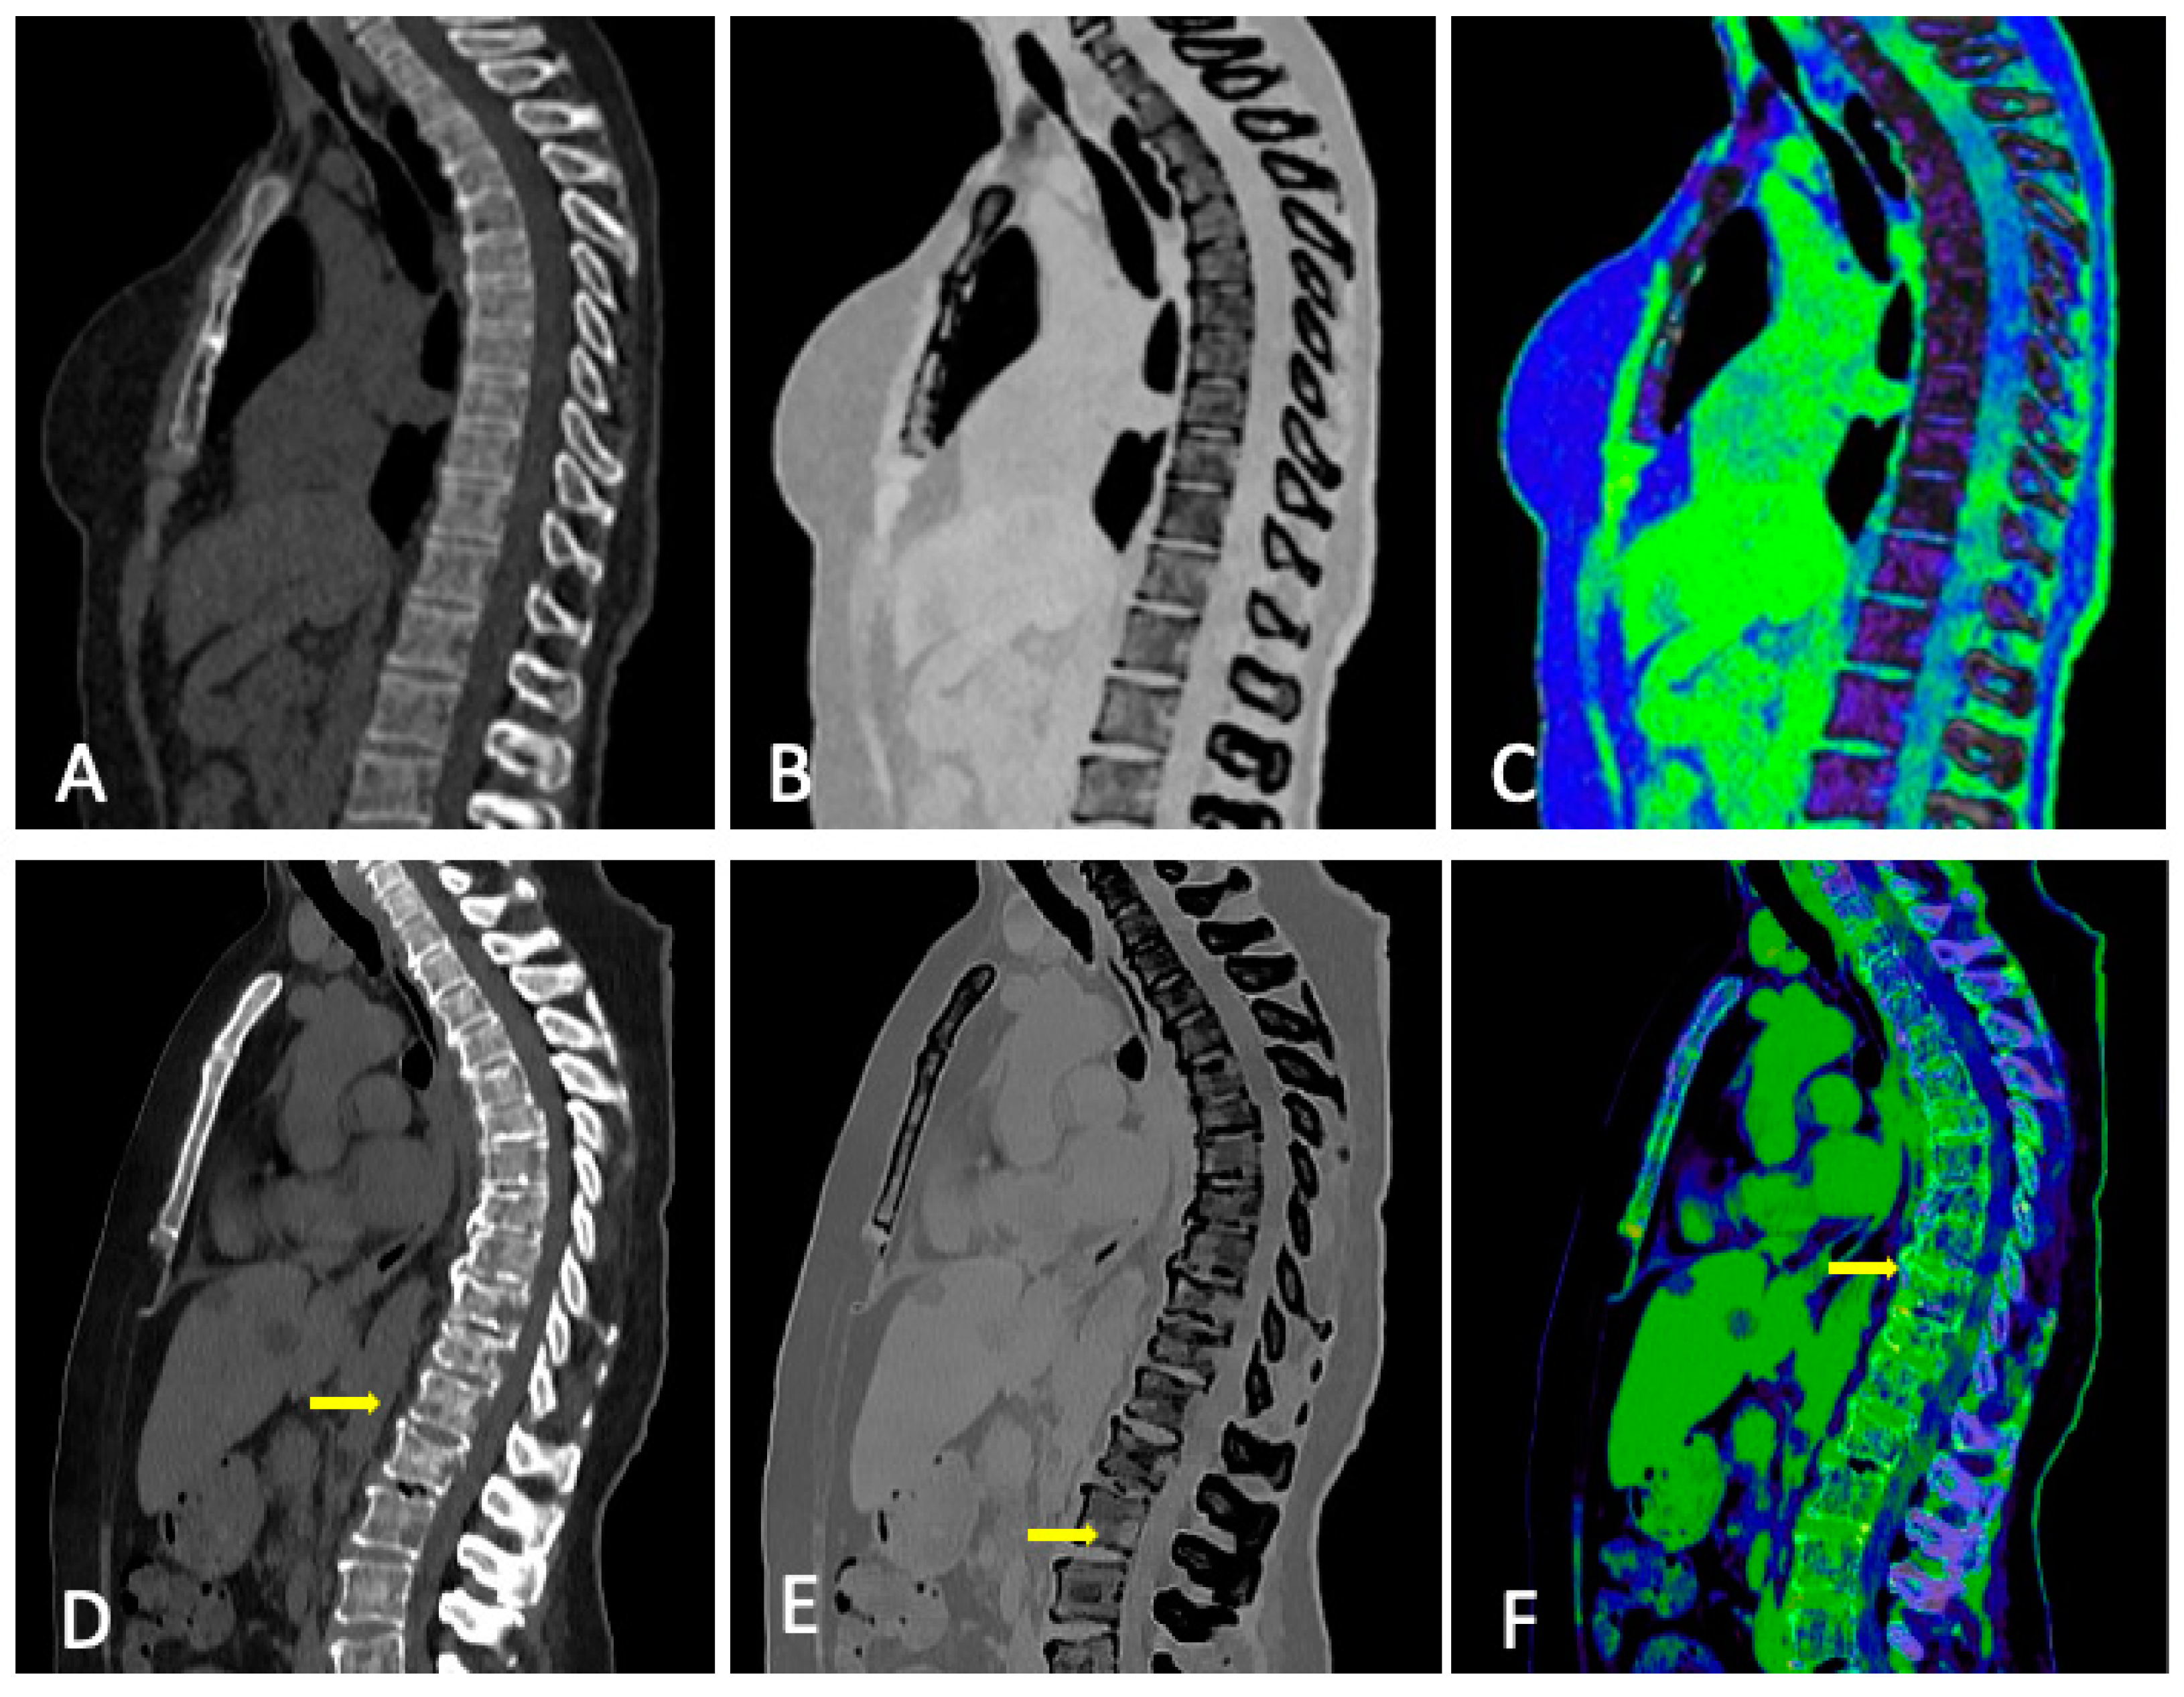

3.3. Role of DECT

3.4. DECT vs. Conventional CT